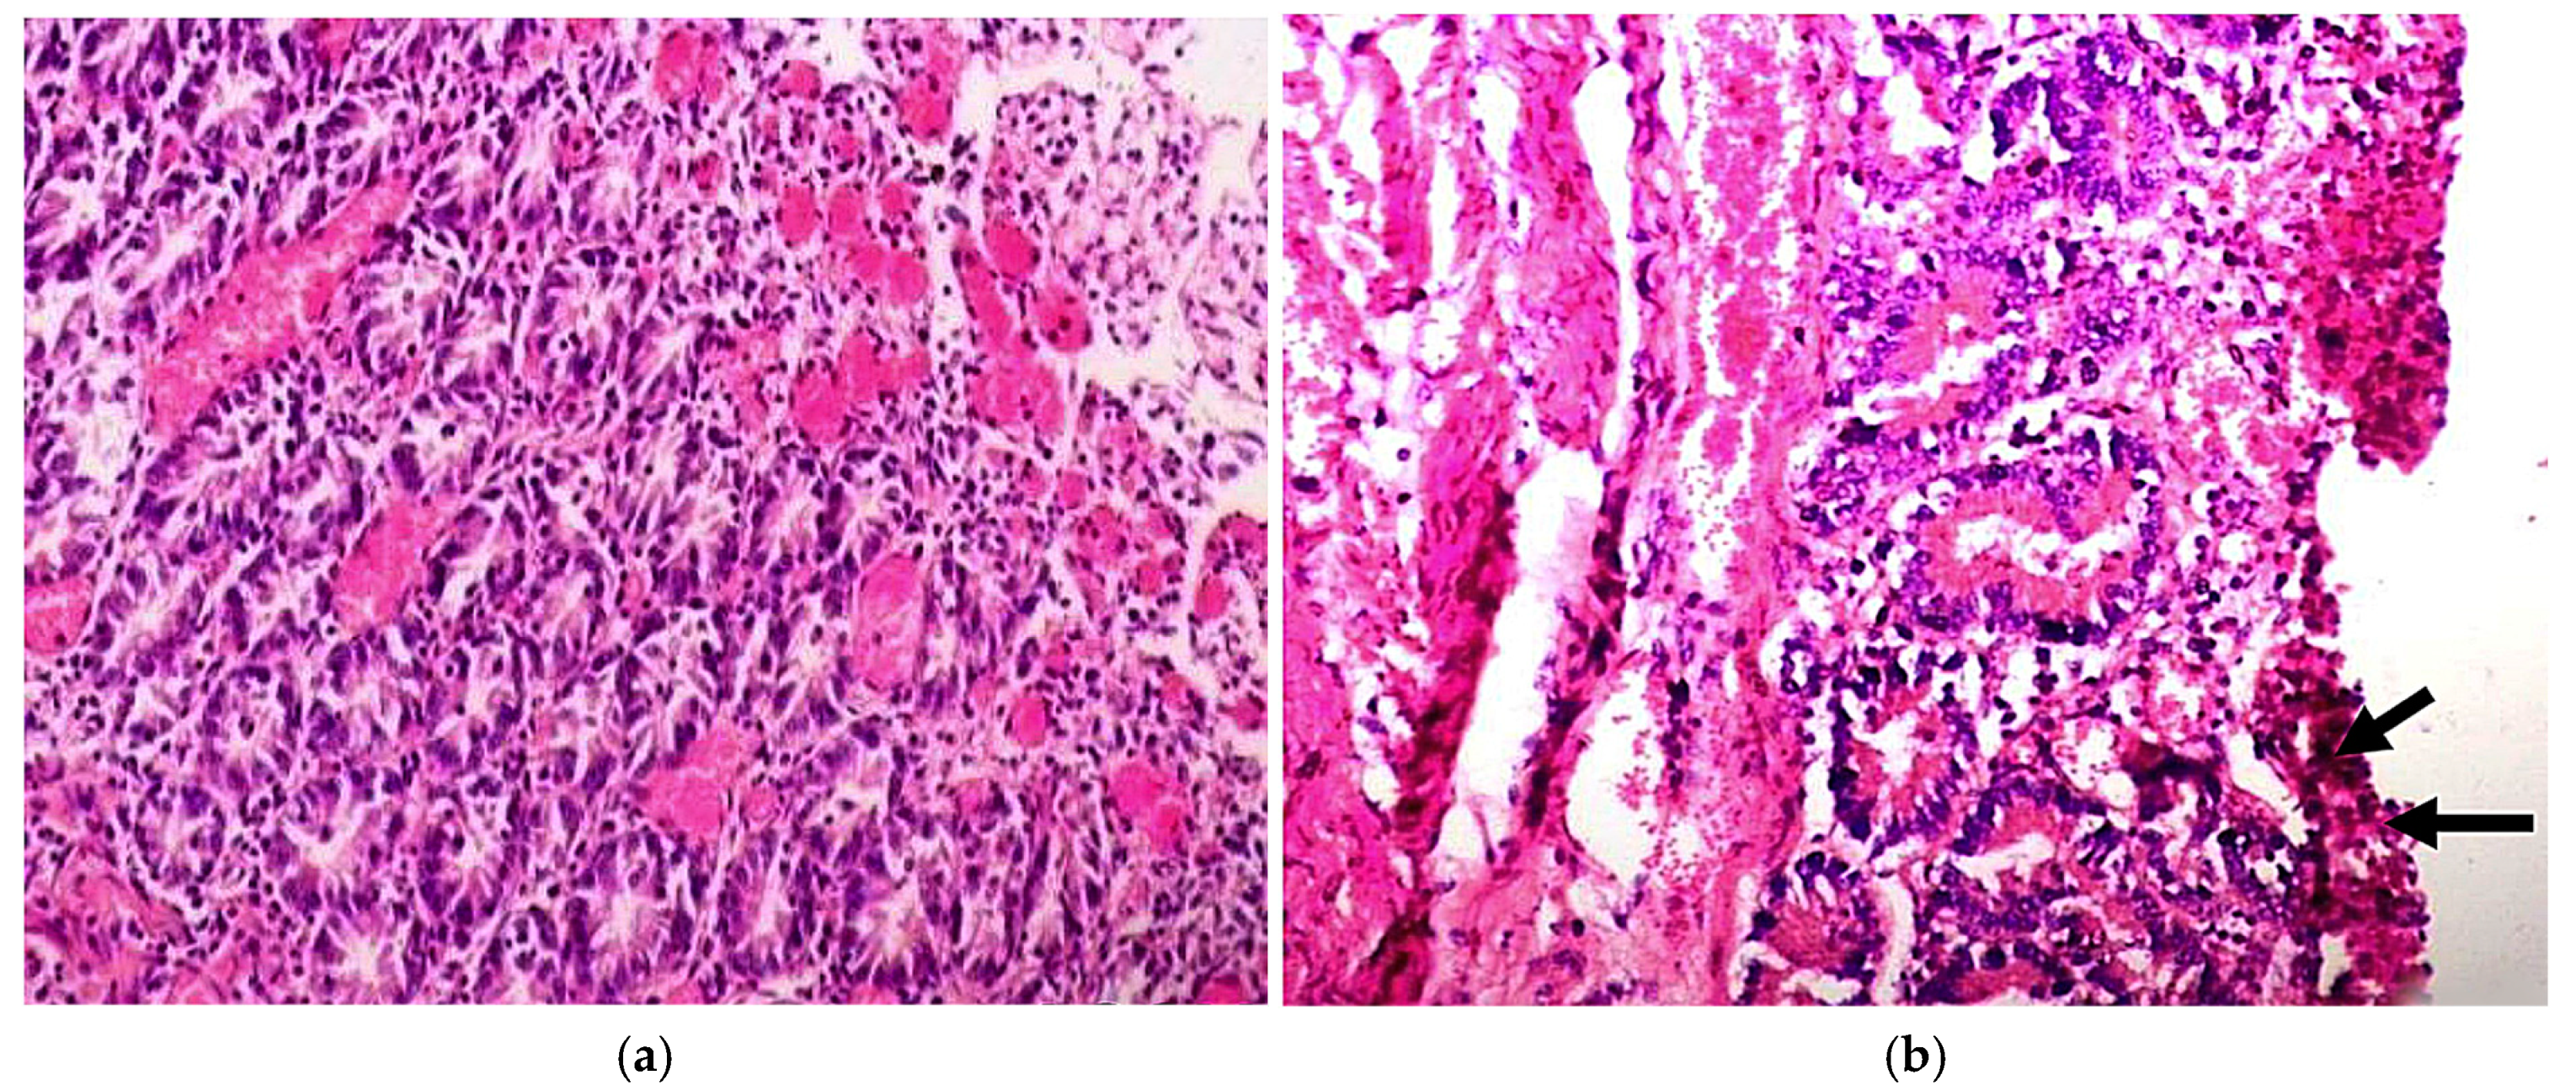

5. Clinical Signs and Pathoanatomical and Histopathological Lesions

- Singh, S.; Singh, R.; Singh, K.P.; Singh, V.; Malik, Y.P.S.; Kamdi, B.; Singh, R.; Kashyap, G. Immunohistochemical and Molecular Detection of Natural Cases of Bovine Rotavirus and Coronavirus Infection Causing Enteritis in Dairy Calves. Microb. Pathog. 2020, 138, 103814. [Google Scholar] [CrossRef]